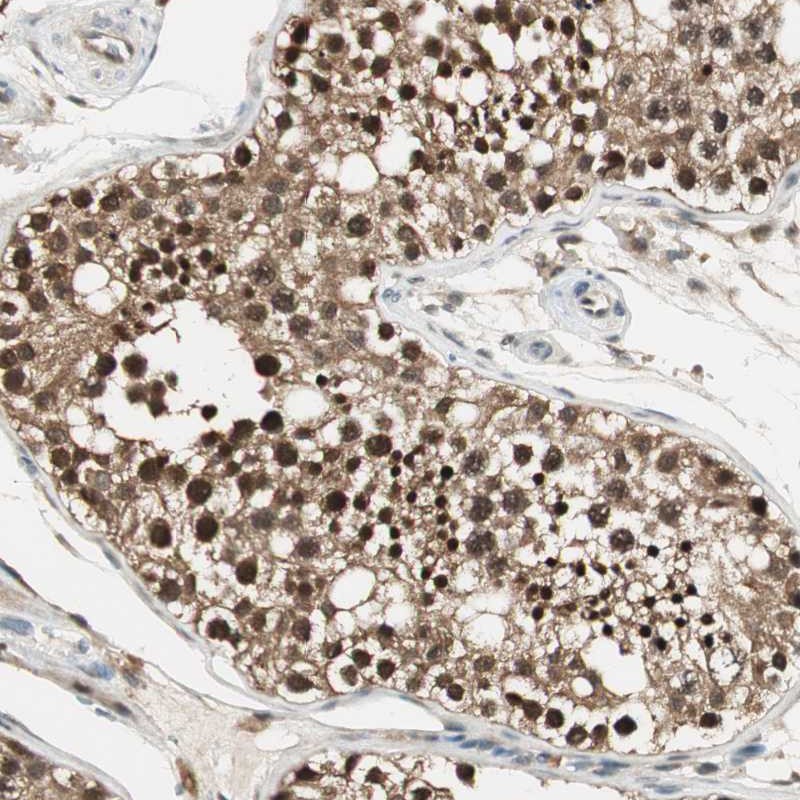

Immunohistochemical staining of human testis shows strong nuclear and cytoplasmic positivity in cells in seminiferus ducts.